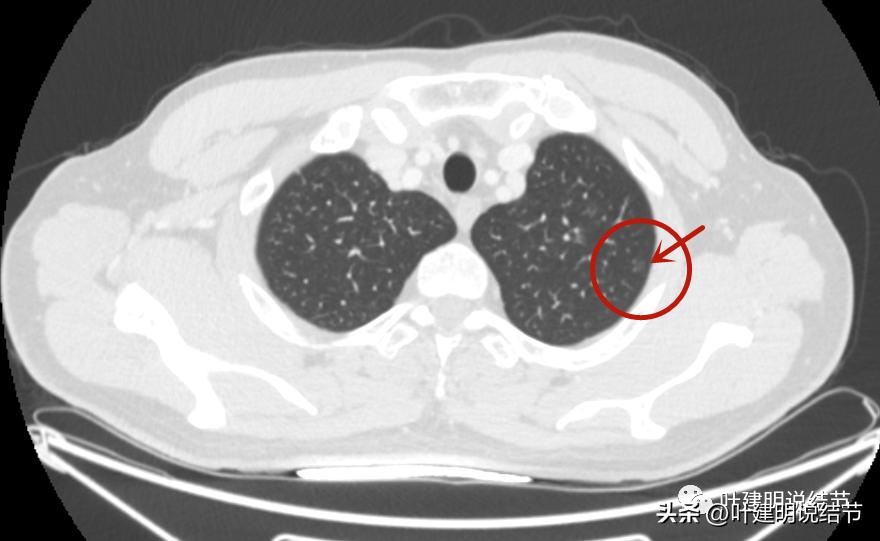

病灶1:左上叶结节

病灶出现,密度很淡,不仔细都看不太出来。

轮廓相对较清,是有结节在,密度低。

边上有小血管贴着,但病灶本身密度确实低。

病灶血管贴边,瘤肺边界较清。

左侧磨玻璃结节红色圈起来的瘤肺边界清,有血管贴边,但整体密度低,没有实性成分,考虑仍是不典型增生或原位癌阶段,近期风险低,个人觉得最好先随访,因为可能很多年不变的,而且也可能再检出新的结节来。况且随访有进展再干预,效果也是一样的。右侧结节也是肿瘤范畴,但风险一样不高,建议同样半年到一年复查(其实1年也关系不大的)。意见供参考!